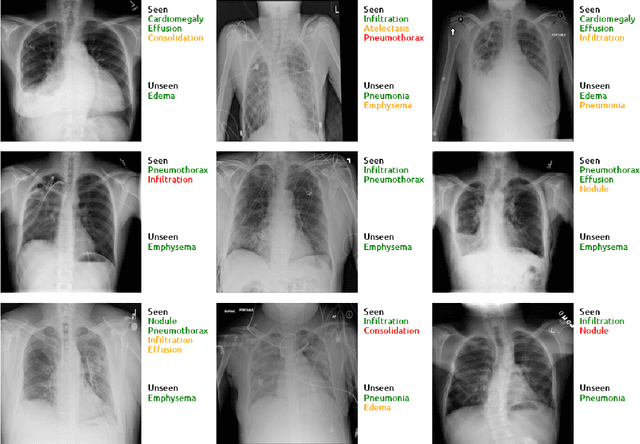

Abstract:Despite the success of deep neural networks in chest X-ray (CXR) diagnosis, supervised learning only allows the prediction of disease classes that were seen during training. At inference, these networks cannot predict an unseen disease class. Incorporating a new class requires the collection of labeled data, which is not a trivial task, especially for less frequently-occurring diseases. As a result, it becomes inconceivable to build a model that can diagnose all possible disease classes. Here, we propose a multi-label generalized zero shot learning (CXR-ML-GZSL) network that can simultaneously predict multiple seen and unseen diseases in CXR images. Given an input image, CXR-ML-GZSL learns a visual representation guided by the input's corresponding semantics extracted from a rich medical text corpus. Towards this ambitious goal, we propose to map both visual and semantic modalities to a latent feature space using a novel learning objective. The objective ensures that (i) the most relevant labels for the query image are ranked higher than irrelevant labels, (ii) the network learns a visual representation that is aligned with its semantics in the latent feature space, and (iii) the mapped semantics preserve their original inter-class representation. The network is end-to-end trainable and requires no independent pre-training for the offline feature extractor. Experiments on the NIH Chest X-ray dataset show that our network outperforms two strong baselines in terms of recall, precision, f1 score, and area under the receiver operating characteristic curve. Our code is publicly available at: https://github.com/nyuad-cai/CXR-ML-GZSL.git